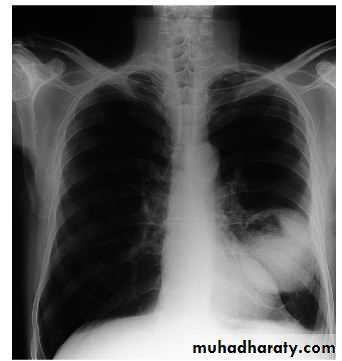

Radiology

• Unilateral hilar enlargement• Peripheral pulmonary opacity

• Lung, lobe or segmental collapse

• Pleural effusion

• Broadening of mediastinum,

• Enlarged cardiac shadow,

• Elevation of a hemidiaphragm

• Rib destruction

LUNG CANCER - Dr. Mustafa Nema- Baghdad College of MedicineRadiology

The most frequent finding is a mass in the lung field.Secondary manifestations seen on the CXR include lobar collapse, total lung collapse, pneumonitis because of endobronchial obstruction, elevation of the hemidiaphragm,

Elevation of the hemidiaphragm

lobar collapse & pneumonitis